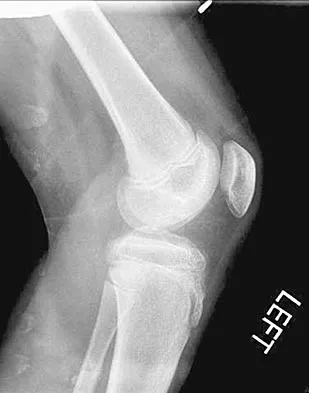

A 28-year-old man has had a 2-year history of progressive lateral ankle pain. History reveals that he underwent a triple arthrodesis at age 13 for a tarsal coalition. The pain has been refractory to braces, custom inserts, and nonsteroidal anti-inflammatory drugs. Weight-bearing radiographs of the ankle and foot are shown in Figures 3a through 3d. Surgical management should include which of the following?